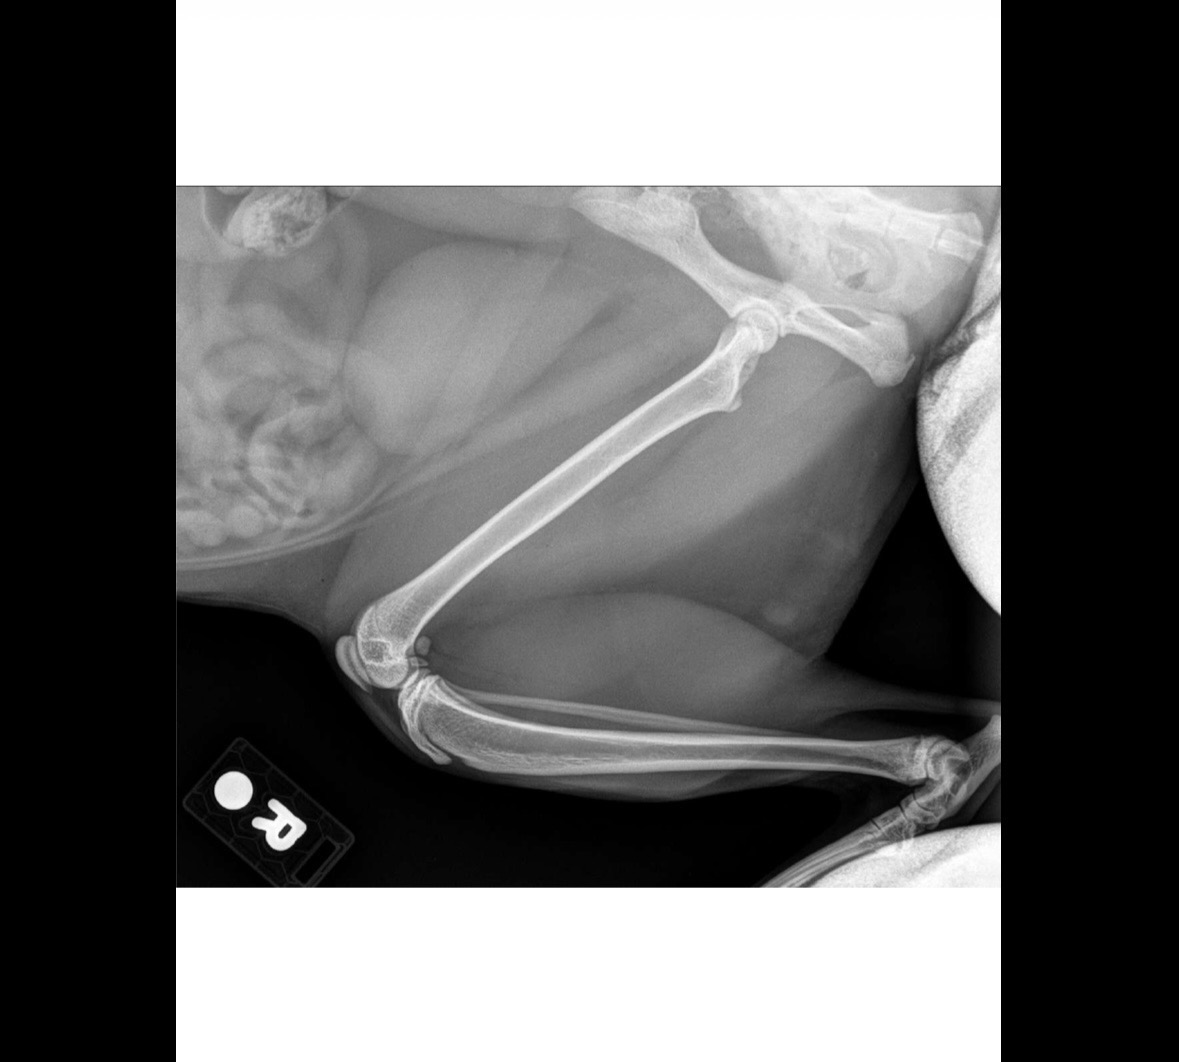

Luna had a fractured hip and he just got surgery, a procedure called a femoral head ostectomy (FHO). The cost of the surgery itself and the aftercare is unfortunately more than we can handle. I hate asking for money, especially from strangers CRYING but folks it’s actually sad, we could really use your help :/